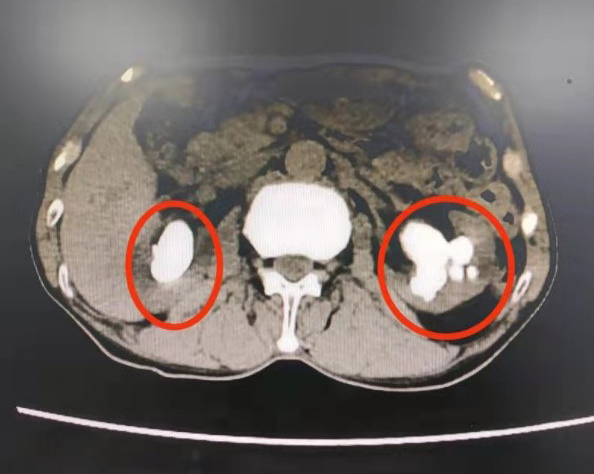

红圈内为患者两侧肾脏及结石

阿伯出现的结石叫铸型结石,也称鹿角型结石,因为其形状像鹿角而得名。这种结石一般体积较大,但如果未引起肾盏肾盂的梗阻或感染,则可能长期存在没有任何症状。同样的,如果结石较小,位于肾盏相对固定且未引起肾盏梗阻,也可能无明显症状,只能体检时偶然发现。